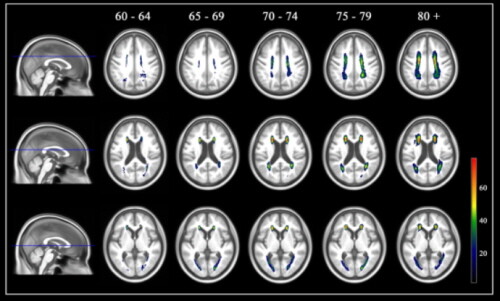

이 확률지도를 이용하면 대뇌 백질고강도신호가 60~64세, 65~69세, 70~74세, 75~79세, 80세 이상의 다섯 개 연령군 중 어디에 해당하는지를 판정할 수 있다.

백질고강도신호가 실제 나이와 동일한 케이스, 실제 나이보다 적은 케이스, 실제 나이보다 많은 케이스 총 3명을 선정해 백질고강도 신호를 백질고강도신호 확률지도에 겹쳐 표기했을 때, 백질고강도신호 연령이 실제 나이보다 많은 사람에게서는 확률지도 범위를 넘어서는 신호가 관찰됐다.

| ▲ 연령별 한국 노인 백질고강도신호 확률지도 (사진=분당서울대병원 제공) |